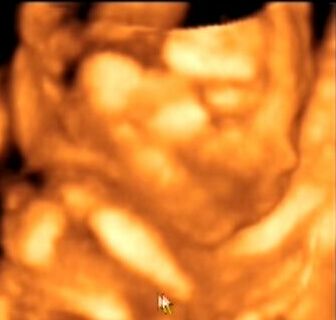

4 d uh: nem szoktam ennyire beajulni a dolgoktol, foleg mert az en orvosom is hipiszupi, DE! Anya nyiregyhaza mellett lakik es a nyiregyi barataink ajanlottak, h menjek el az o orvosukhoz 4d uh.-ra. mivel itt bp.-en a sote-ra jarok es ott nem engedik be a ferjem, na meg anya sem latott meg uh.-t, igy ugy dontottem elmegyunk. haaaaaaaaaaat olyan alapos, reszletes uh.-ban es vizsgalatban volt reszem; figy: pl megmerte a fej, agykamrak, megnezte h nincs farkastorok, nyulszaj, megnezete a tudot (mert mindnet), h nincs rekesziz.serv, sziv, gyomor, vese, hugyh., hugyvez, kez es lab csontok, de ugy, h megneztuk a 2 labszarcsontot ... eeessss azt is nezte h amikor nyel a gyomor tartalma hogyan valtozik es elmondta h pl ha a vese x mm-nel kisebb v nagyobb, akkor az milyen gen betegsegekre utalna.

mar eleve azzal kezdte a doki, h beteg gyerek nem kerul ki a keze alol, mert o mindnet nez es eszrvesze -sokat jar kulfoldre konferenciara!

na jo nem fokozom tovabb EDDIG MINDEN RENDBEN AZ EDES LINIKENKKEL!!!!!!!!!!!